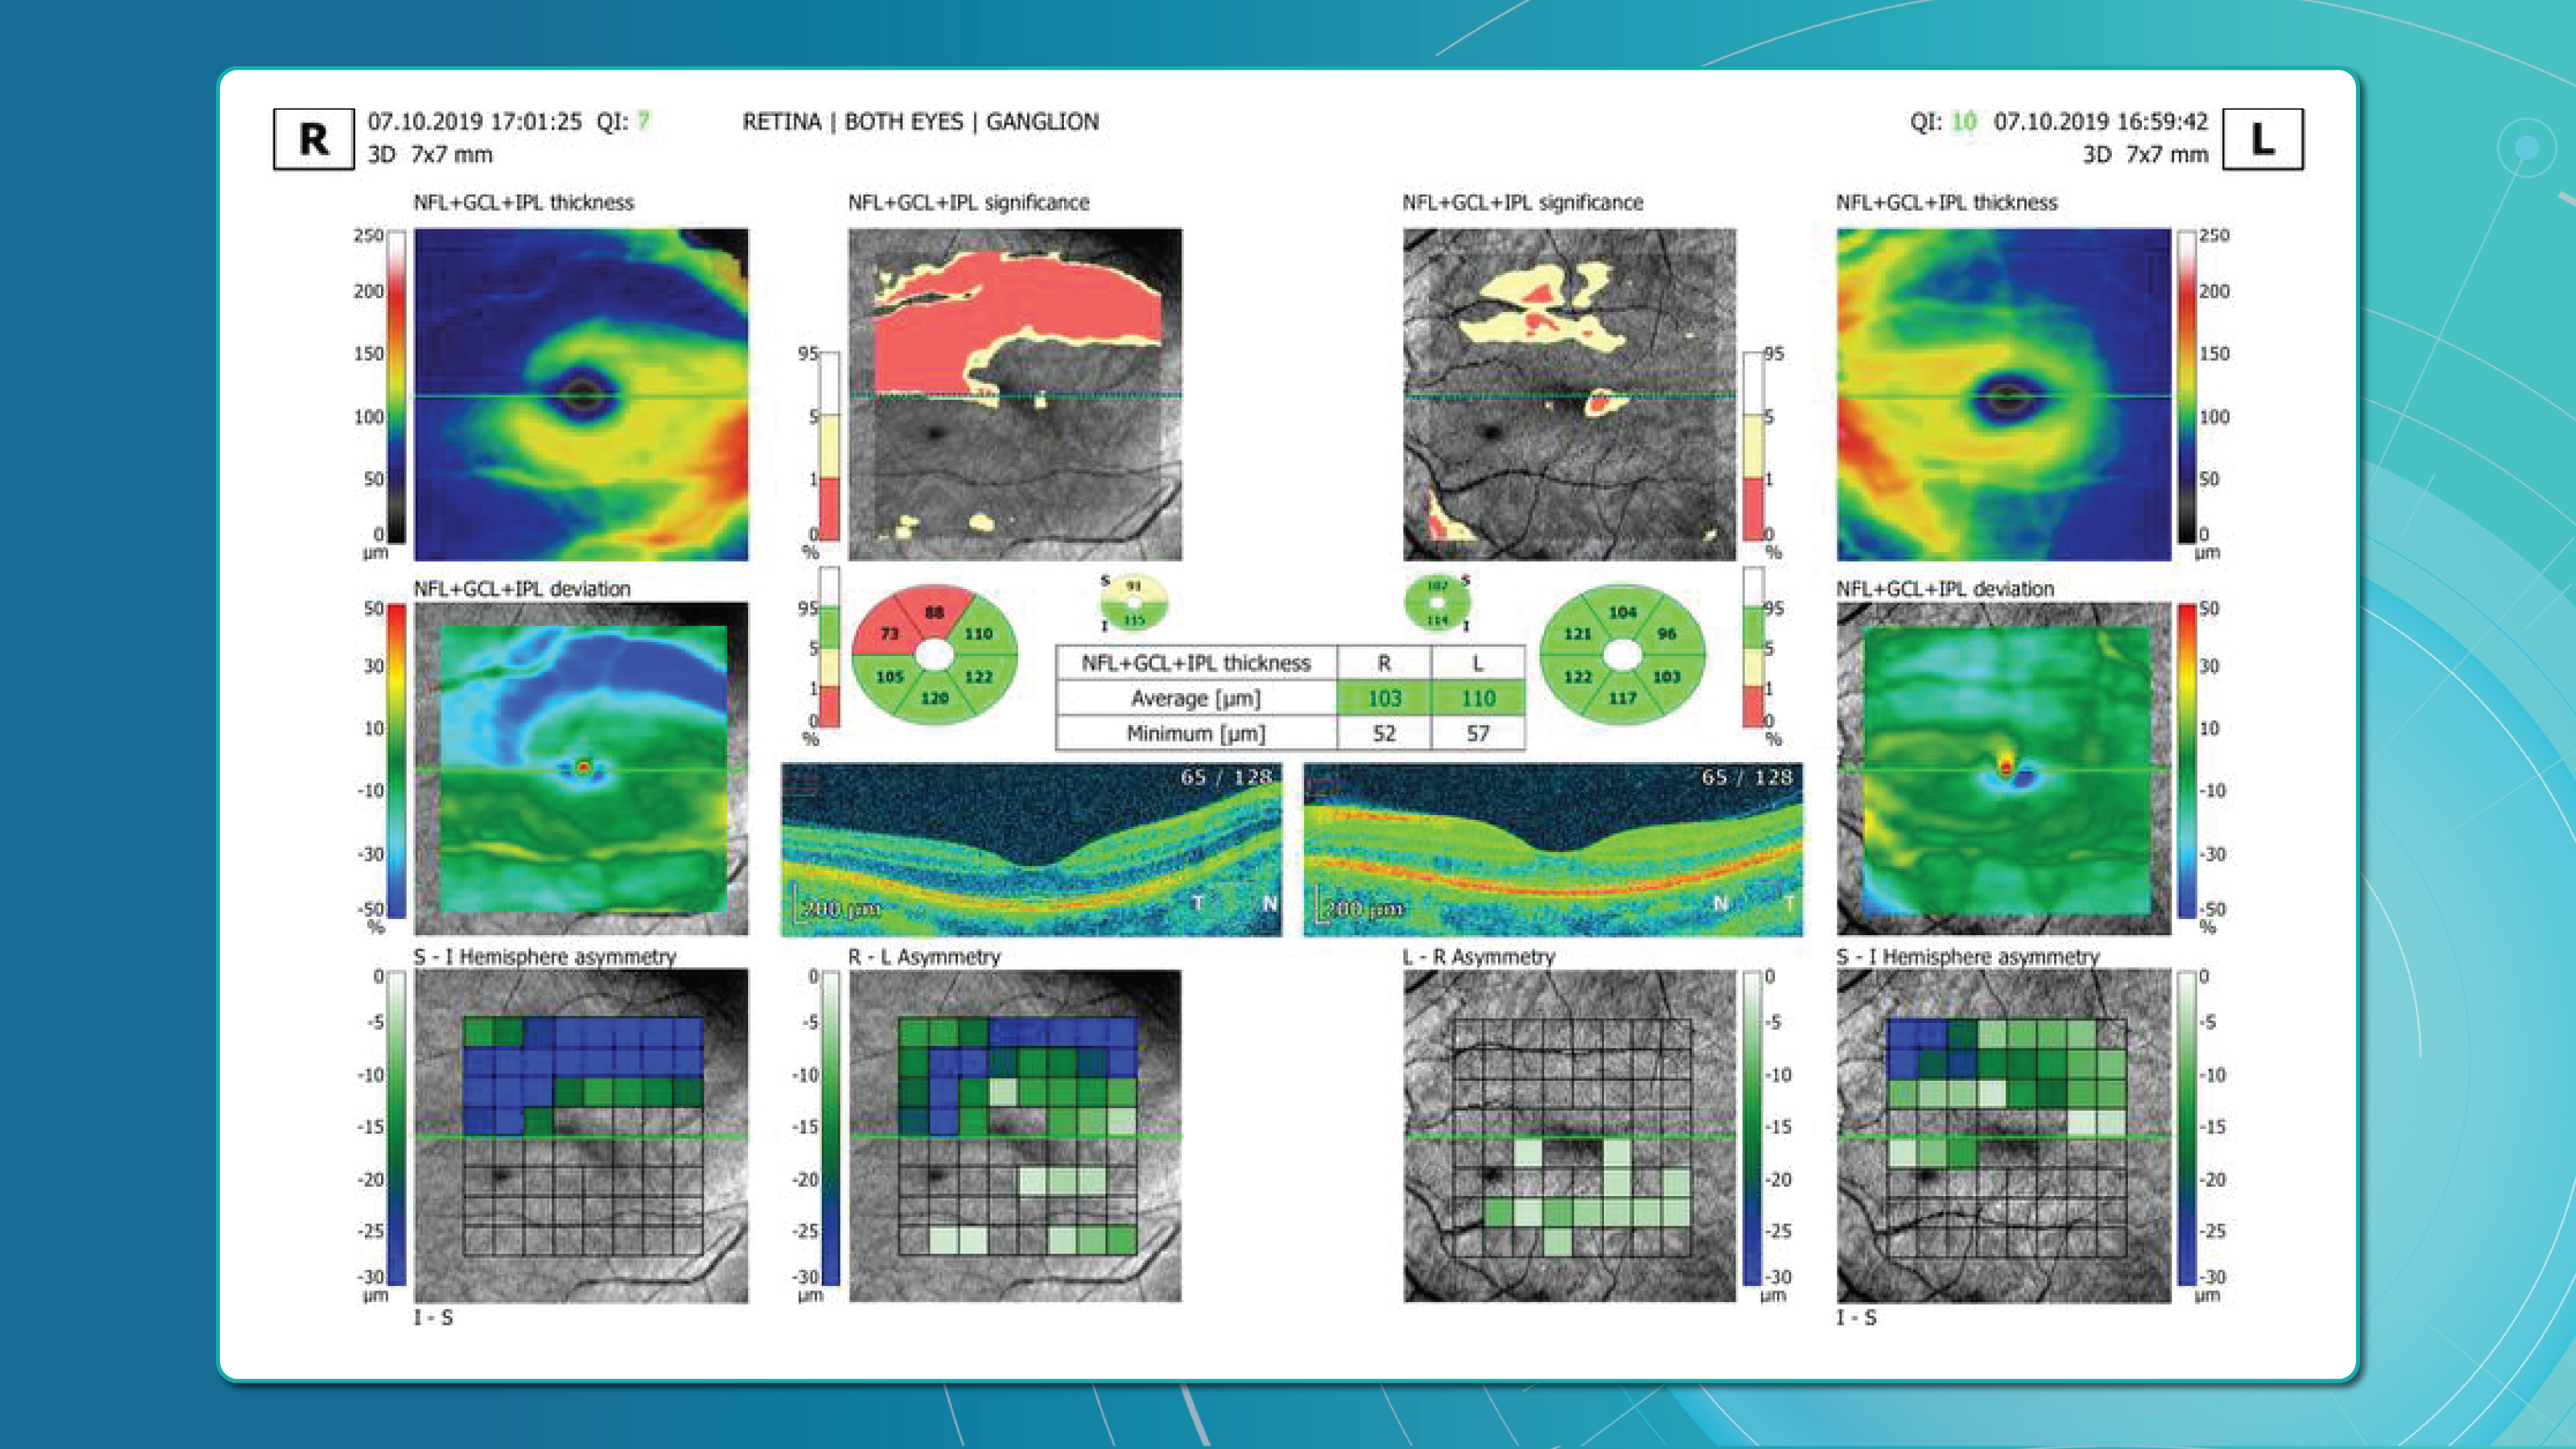

Dr. Maria Sampalis, OD, the owner of Sampalis Eye Care, Rhode Island, utilizes two such programs in her practice. To support her specialization in dry eye management, she employs CSI Dry Eye. Additionally, she uses Altris AI, an AI-powered platform for OCT scan analysis, to provide a second opinion and enhance diagnostic accuracy.

Her patients also appreciate Altris AI, which analyzes OCT scans for over 70 pathologies and biomarkers while also calculating the risk of developing glaucoma.

Eye Place, an optometry center in Columbia, also leverages Altris AI, among other cutting-edge technologies. They capture images using the Topcon Maestro2 OCT and use Image Net6 software to export DICOM files to the Altris AI platform.

Beyond AI-powered OCT analysis, Eye Place utilizes state-of-the-art diagnostic tools, such as 3D OCT equipment, to screen for serious conditions, including glaucoma, diabetes, and macular degeneration. Furthermore, they work with AdaptDX Pro, a technology capable of detecting macular degeneration earlier than traditional methods.

For instance, AI today can assess the early risk of glaucoma based on the GCC asymmetry measurements. Here is how AI-powered OCT workflow would look.

AI-assisted readings of OCT scans are already helping not only with pathology detection but also with the analysis of its progression or response to treatment. This represents a new approach to monitoring, where practitioners no longer need to sift through various patient notes but can directly compare reports from previous examinations and observe how, for instance, shadowing has changed in micrometers.

Millions risk irreversible vision loss due to undiagnosed glaucoma, underscoring the need for improved early detection. Current tests often rely on observing changes over time, delaying treatment assessment and hindering early identification of rapid disease progression. OCT frequently detects microscopic damage to ganglion cells and thinning across these layers before changes are noticeable through other tests. However, the earliest signs on the scan can still be invisible to the human eye.

AI algorithms offer insights into glaucoma detection by routinely analyzing the ganglion cell complex, measuring its thickness, and identifying any thinning or asymmetry to determine a patient’s glaucoma risk without additional clinician effort.